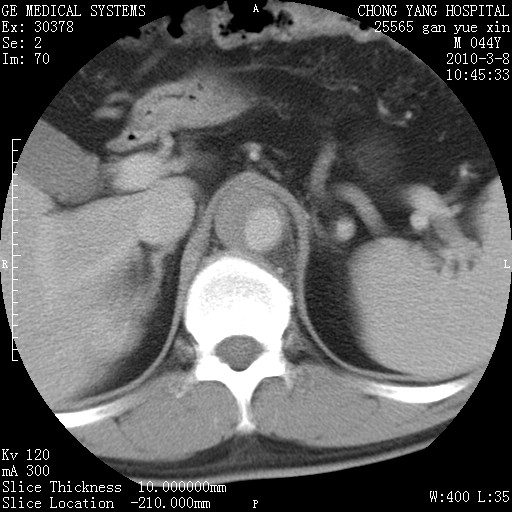

标题: CT24940:主动脉增强,典型病例。 [打印本页]

标题: CT24940:主动脉增强,典型病例。

夹层动脉瘤。

动脉夹层

夹层动脉瘤,典型

主动脉夹层。

动脉夹层的分型:

⒈debakey分型:根据主动脉夹层累及部位,分为三型:ⅰ型:原发破口位于升主动脉或主动脉弓部,夹层累及升主动脉、主动脉弓部、胸主动脉、腹主动脉大部或全部,少数可累及髂动脉。ⅱ型:原发破口位于升主动脉,夹层累及升主动脉,少数可累及部分主动脉弓。ⅲ型:原发破口位于左锁骨下动脉开口远端,根据夹层累及范围又分为ⅲa,ⅲb。ⅲa型:夹层累及胸主动脉。ⅲb型:夹层累及升主动脉、腹主动脉大部或全部。少数可累及髂动脉。

⒉stanford分型:a型:夹层累及升主动脉,无论远端范围如何。b型:夹层累及左锁骨下动脉开口以远的降主动脉。

夹层动脉瘤,少量胸水

夹层动脉瘤;左侧少量胸腔积液。

典型主动脉夹层。